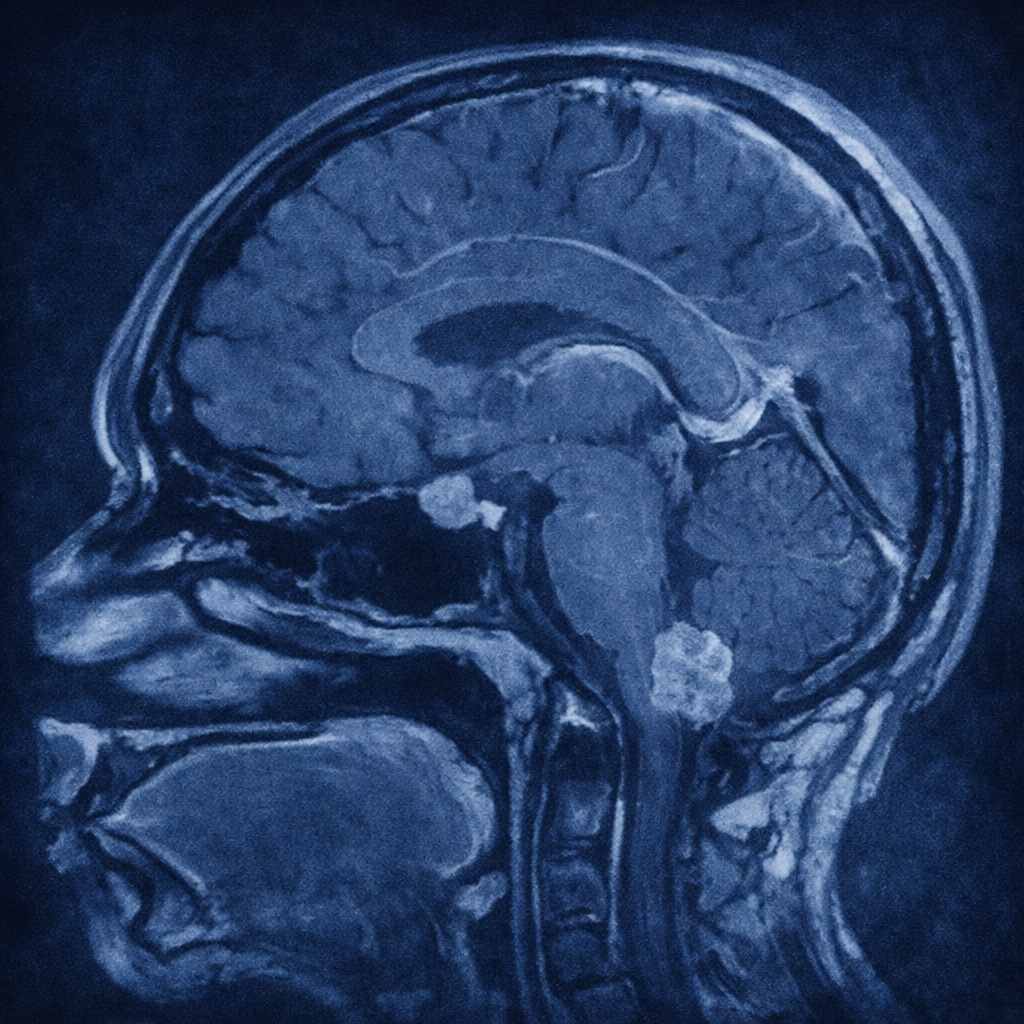

El estudio inicial para el diagnóstico de estos tumores es la resonancia magnética cerebral con gadolinio o medio de contraste. En este estudio se identifica normalmente un tumor en el interior del 4.° ventrículo, que se origina en el techo del mismo. Debido a su localización, es frecuente encontrar hidrocefalia por la obstrucción del flujo del líquido cefalorraquídeo. La resonancia es un estudio muy importante para evaluar la diseminación tumoral por el líquido cefalorraquídeo, puesto que encuentra “siembras” tumorales a distancia.